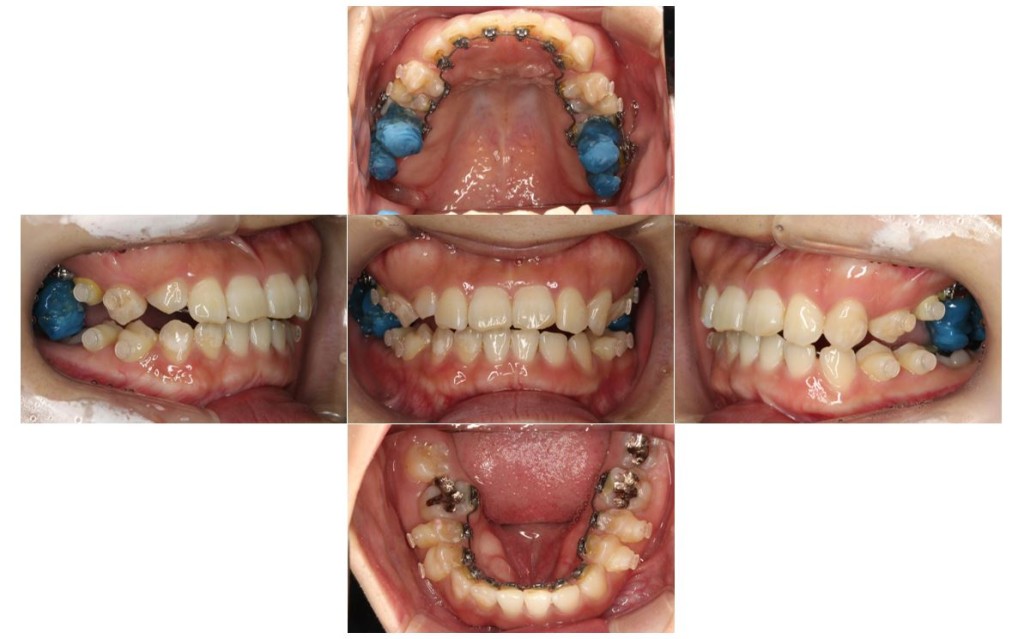

当院の症例

| 主訴 | ずっと気になっていた見た目、噛み合わせを含めて受け口を治したい。期間はかかってもいいので、外科手術をしないで歯列矯正だけで改善したい。 |

| 矯正の装置 | 裏側矯正から治療途中に表側矯正へ変更 |